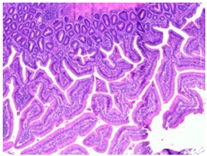

| Observations | Picture 40× | Picture 400× | |

|---|---|---|---|

| Samples from the CTL group | Inflammatory cellular infiltrates in the mucosa (with the participation of heterophils) Single mitotic figures in crypt epithelial cells Connective tissue hyperplasia |  |  |

| |||

| SNCE group | Scant infiltration of inflammatory cells in the mucosa (with the participation of heterophils) and the formation of individual lymphatic nodules Numerous goblet cells/heavily filled with mucus Vesicular nuclei of intestinal crypt epithelial cells; numerous mitotic figures |  |  |

|